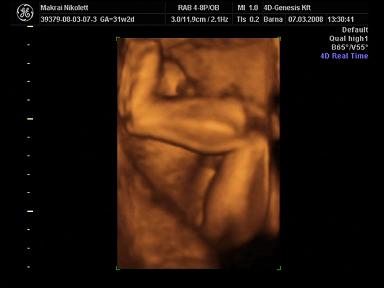

2008.03.07 19:57